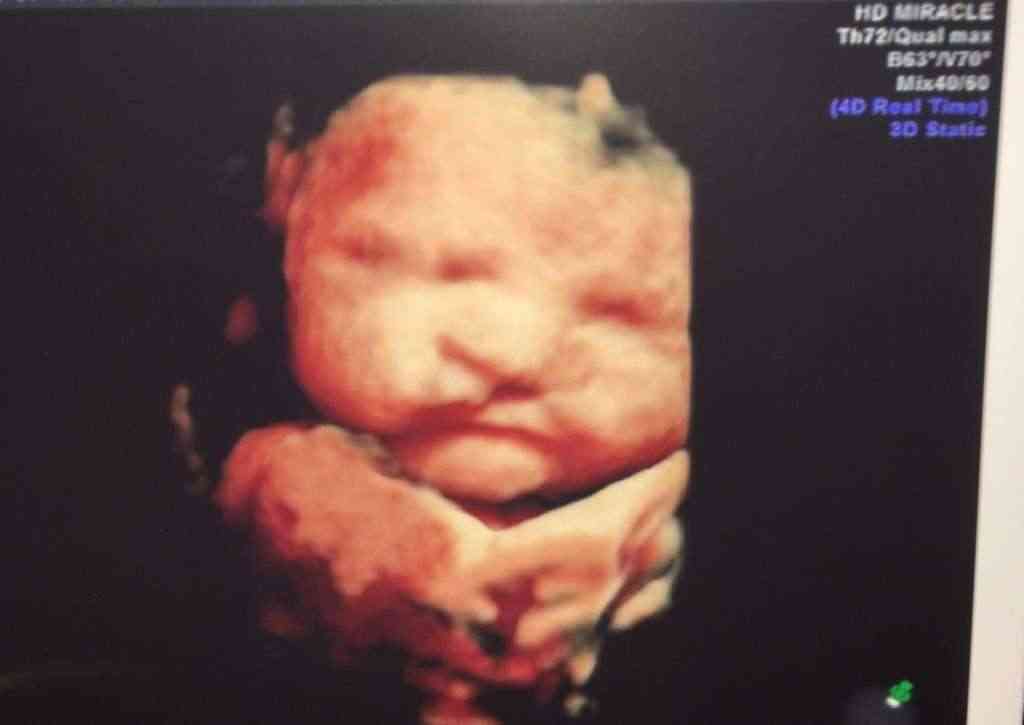

Growing up you never imagined yourself being a mother to a child who had complications. You imagined being a mom to normal children, raising perfect little human beings and loving every ounce of it. My first son was like that, a total dream. Along came baby #2 for our family. From day one of this pregnancy something felt wrong. I always knew that I was going to have a miscarriage. I developed depression during the first 15 weeks of pregnancy because I knew something was wrong. With each ultrasound came the feeling that there would be no heartbeat. We hit 15 weeks and I finally accepted that everything was okay. I finally announced our pregnancy to the social media world and we found out that baby #2 was another boy! We were ecstatic to say the least. We went in for a 16 week ultrasound and it took forever. The tech went over everything and I was slightly confused because this wasn’t our anatomy scan. She then said…”Your baby has a complication.” If you have never (which I hope you haven’t) heard those words, they are heart dropping, gut wrenching, horrible words to come by. I instantly broke out in tears. She explained that she saw a cleft lip and possible palate. I was mortified, embarrassed, scared, every emotion went through my body in that moment. Our doctor came and talked to us about it and sent us to see a specialist. Few months went by and we met with our specialist. After a very long and detailed ultrasound.. He came to us with 100% saying he had a cleft lip and palate…but…. There was more.

Our baby had a left brain ventricle that was dilated. We went into a private room and he pulled out a book and went over every possible outcome with us. We were told our baby may not survive. This ventricle was a sign of Trisomy. (you can read more about our full story on my blog HERE)

After several months and several ultrasounds our precious baby boy was born. Wilder Bigt made his appearance at 8 lbs 10 oz and 21 inches long. He showed no signs of trisomy, down syndrome, etc. He had a left unilateral complete lip and palate but he was perfect. With a cleft lip came several and I mean several long nights. The first month was rough, and looking back on it.. It was such a blur. We were on a strict 2 hour feeding schedule. He wasn’t able to breastfeed because he couldn’t suck like a normal baby. We had special bottles for him, he couldn’t take a binky. He wasn’t a typical baby. Adjusting to two kids was tough but having a child that required my attention 24/7 was even tougher. We met with our surgeon who was on the other side of the state and got the game plan for the next year. Wilder needed 1 surgery between 3-6 months, 12-18 months, 2-4 and 5-7 then there may be some occasional surgeries in his older years. We got what is called a NAM device at 1 month.